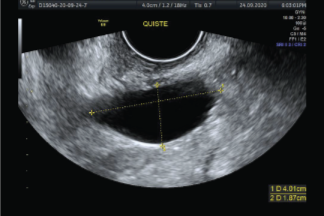

Ecografía Vaginal, este es un examen de diagnóstico, donde se obtienen imágenes de los órganos internos como: útero, trompas de falopio, ovarios, cuello del útero y vagina. En este estudio se puede detectar:

• Quistes y fibromas